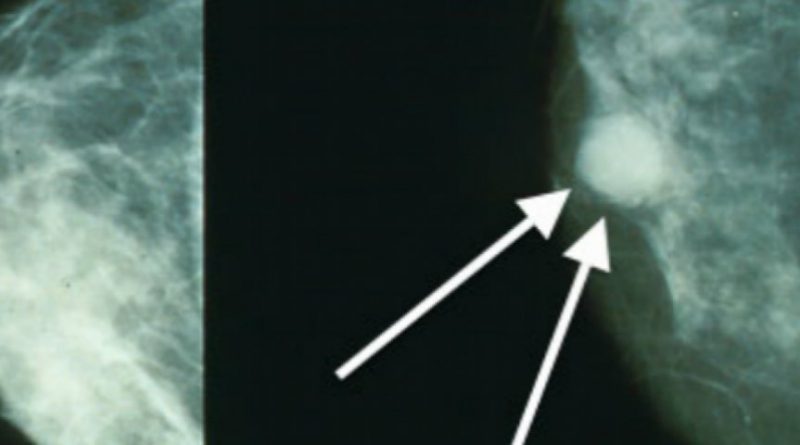

Las mamografías, que alguna vez fueron consideradas una de las principales armas de la medicina para anticipar la tragedia del cáncer de mamá en miles de mujeres, hoy sufren cuestionamientos y críticas desde varios ángulos. La promesa de que ayudarían a prevenir y salvar vidas no resultó tan cierta como se creyó.

En las últimas décadas, médicos y agencias de salud han recomendado a las mujeres mayores de 50 años practicarse una mamografía anual o cada dos años para detectar de manera temprana un tumor mamario y ganar tiempo para tratarlo. Un nuevo estudio llevado a cabo en Holanda confirmó resultados previos de trabajos en Europa y Estados Unidos: las introducción de mamografías en el sistema de salud no se ha traducido en reducción significativa en las tasas de mortalidad por cáncer de mama.